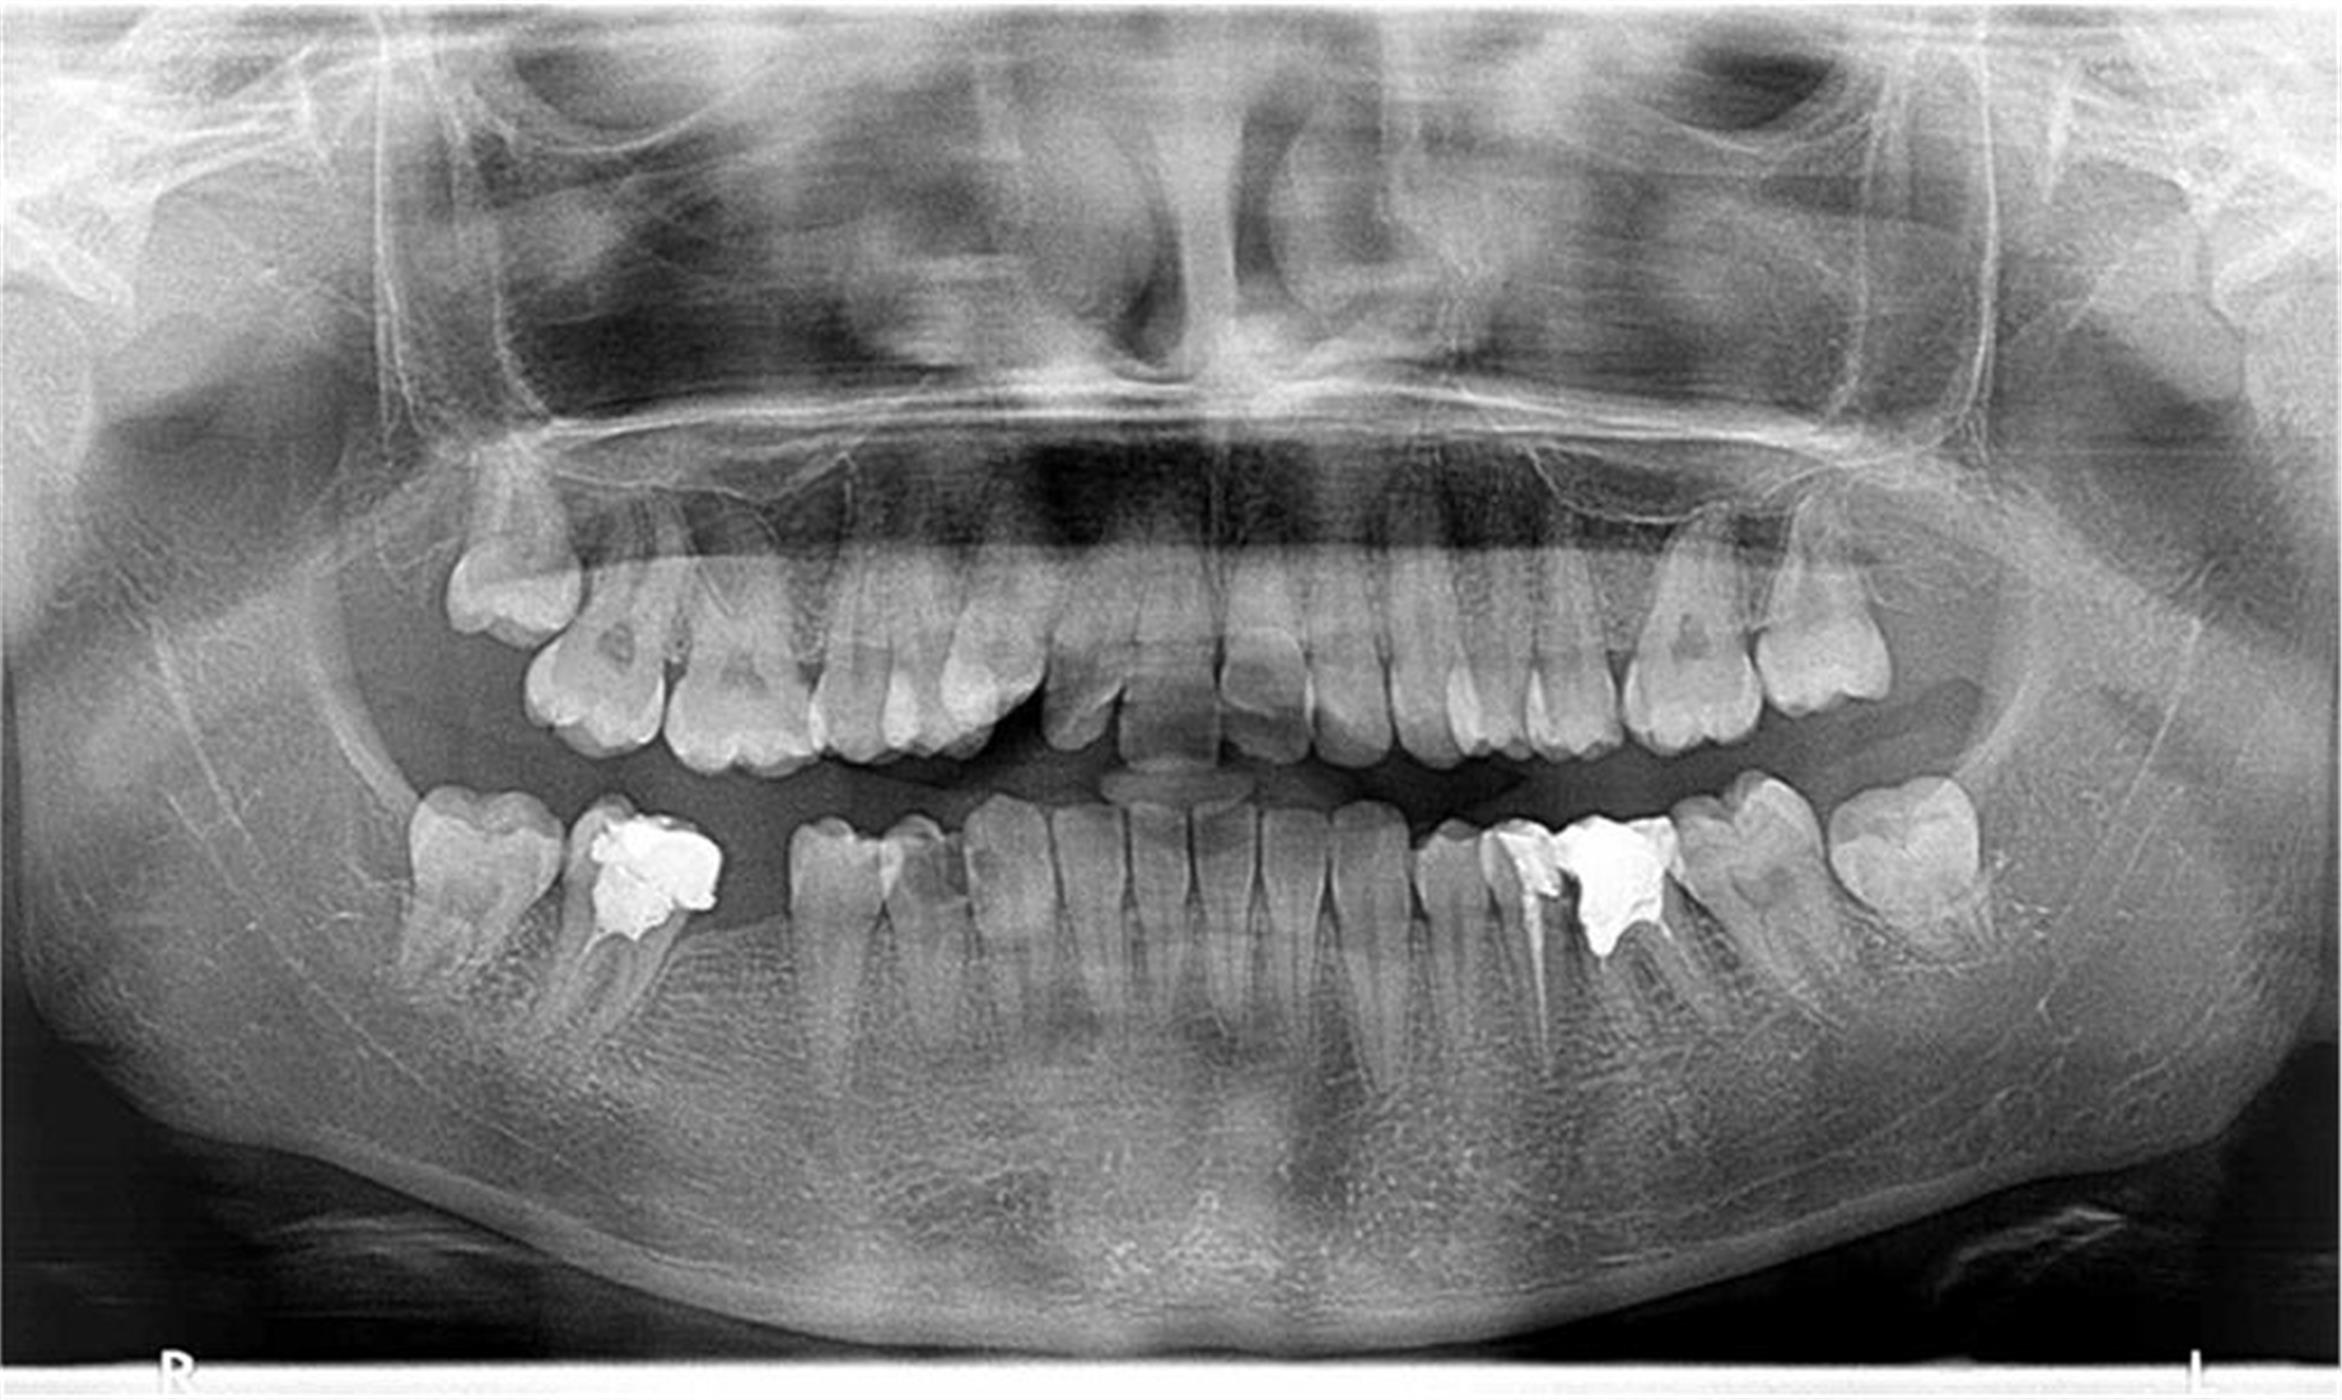

Современата ендодонција е целосно застапена во нашата ординација. Тоа вклучува примена на апекс локатор (за прецизно одредување на должината на коренските канали), системи за машинска обработка на истите (Protaper, Endo eze), системи за иригација (испирање) и дезинфекција на каналите, ласер за комплетна стерилизација, високо квалитено полнење и секако потврда на спроведениот ендодонтски третман со рентген снимка.

ЕНДОДОНЦИЈА

РЕВИЗИЈА